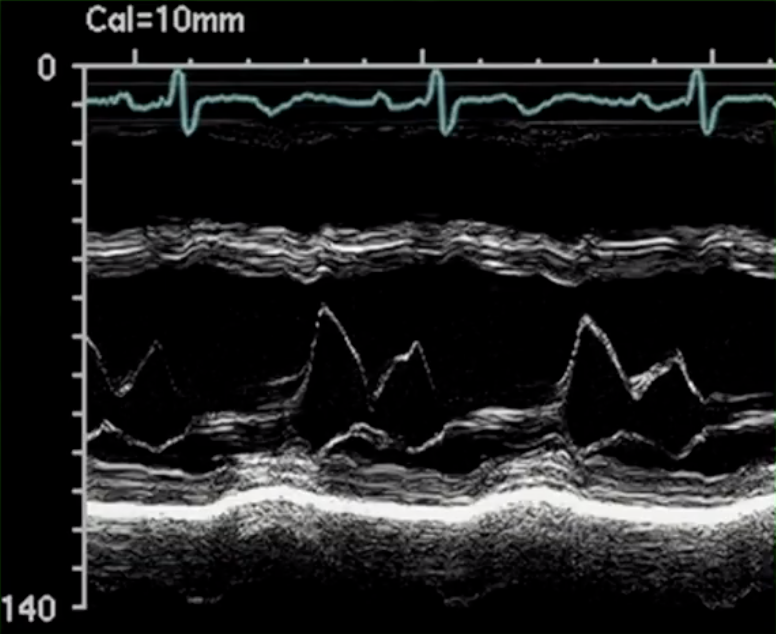

Describe the findings of M mode: